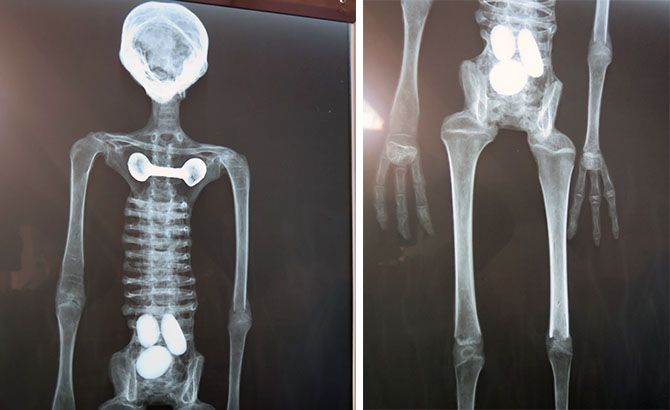

En la exposición también se mostraron las radiografías de Josefina, un reptil preñado con tres huevos. Este es, supuestamente, un Ser No Humano que vivió en Perú hace 1200 años.

Las imágenes de Rayos X también fueron evaluadas posteriormente por Drobyshevsky y por el experimentado paleozoólogo Aleksey Bondarev.

Para el primero, el esqueleto de Josefina está claramente construido a partir de fragmentos de hueso aleatorios. Gran parte del cráneo perteneció alguna vez a un pequeño mamífero que fue despojado de su área facial. Las costillas transversales –ojo a esto- están compuestas de huesos tubulares de un pájaro. De acuerdo a este vídeo, los huesos del muslo se emplearon para representar el húmero y los del húmero real representan los huesos del antebrazo. Los huesos de la tibia fueron reemplazados por huesos del fémur, mientras que las espinillas están hechas de huesos del muslo.

También advirtió que algunas de las falanges de Josefina están al revés, como muestra el vídeo que insertamos a continuación.

Las evidencias son aplastantes pero no acaban aquí. Bondarev advirtió que los huesos del fémur fueron reemplazados por huesos de la espinilla mientras sus partes superiores rozaban contra el borde inferior de la pelvis. “¡Y no tiene articulación, por lo que el pobre no habría podido mover las piernas!” –se lamenta. “Se puede ver claramente que el hueso pseudofémur (el de la derecha en la imagen más arriba) tenía el borde cortado o roto”.

El antebrazo de Josefina está hecho de un solo hueso que es imposible identificar como radio o cúbito. “A mí me parece más bien un hueso de tibia” –reconoce Bondarev.

Esta conclusión, curiosamente, fue confirmada por el doctor González, el radiólogo que seleccionó Maussan para un análisis en vivo con Rayos X y Tomografías y que nadie pareció escuchar.

A Bondarev le sorprendió constatar, además, como ambos antebrazos estaban hechos de huesos distintos. Sus formas, al menos, son significativamente diferentes. Resulta que las primeras pseudofalanges de su mano izquierda y las de su mano derecha están conectadas de forma distinta. Seguro que es por un misterio de la evolución de su planeta de origen (ironía modo on).